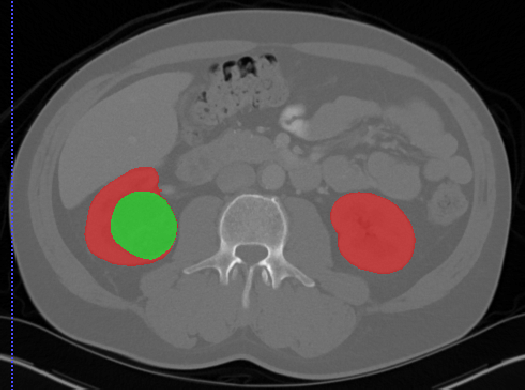

# 肾脏

## Kits19

| 名称 | 标注内容 | 类型 | 模态 | 数量 | 标签格式 | 文件格式 |

| - | - | - | - | - | - | - |

| [Kits19](https://kits19.grand-challenge.org/) | 肾肿瘤 | 分割 | | | | | |

[Aistudio下载](https://aistudio.baidu.com/aistudio/datasetdetail/24582)